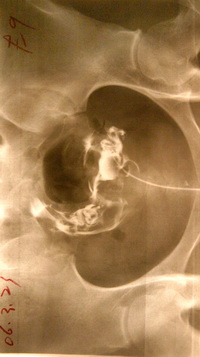

北京家圆医院输卵管造影术 疏通率高达98%以上

家圆造影术一改以往传统检查方法,可视、输卵管是否堵塞、哪里堵塞、病变严重程度等一目了然。造影剂水性,无刺激,身体更容易吸收。、时间短、一次疏通率高!